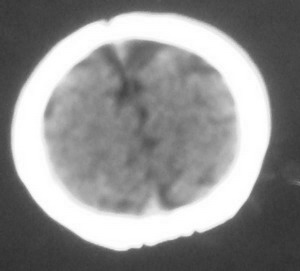

以下是引用dyqct在2008-7-30 17:05:00的发言:[br]考虑:1、胼胝体发育不全;[br] 2、肝豆状核变性(双侧豆状核对称性低密度)。